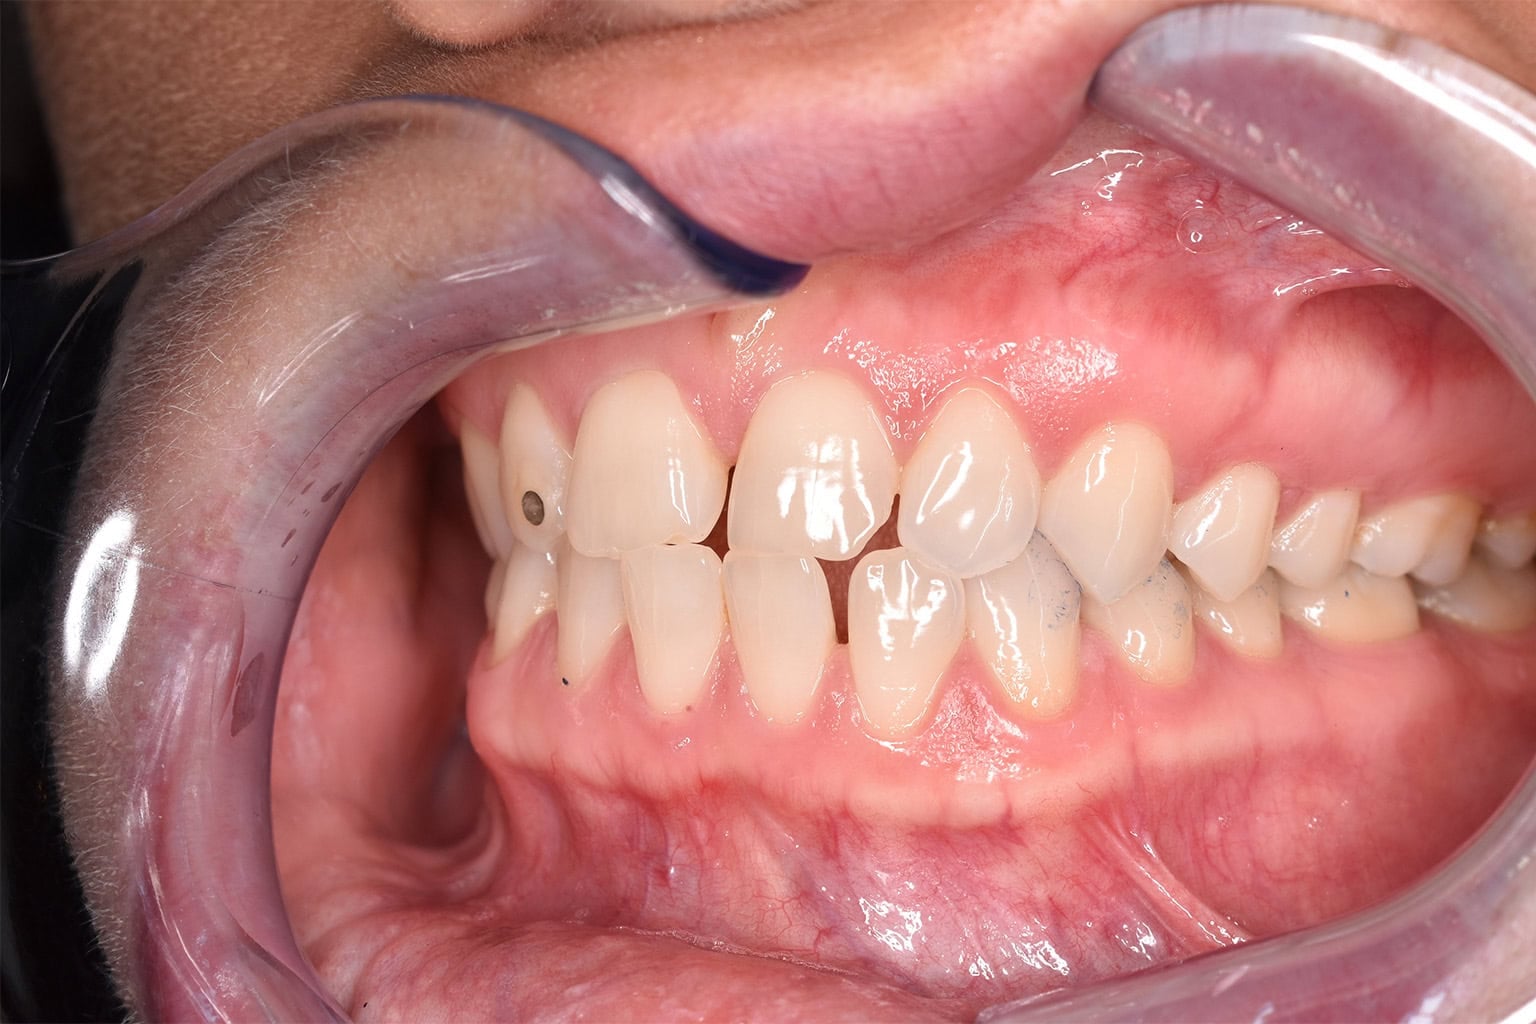

Vorher-Nachher-Ergebnisse

Echte Ergebnisse. Echte Menschen.

Jede Behandlung bei TIEFBLAU Kieferorthopädie ist so individuell wie der Mensch dahinter. In unserer Vorher-Nachher-Galerie zeigen wir Ihnen echte Behandlungsergebnisse aus unserer Praxis in der Kölner Südstadt: Schonend erzielt, präzise geplant und mit dem Anspruch, den wir seit über 40 Jahren an jede Behandlung stellen.

Die Bilder geben Ihnen einen Eindruck davon, was moderne Kieferorthopädie leisten kann, ob bei Kindern, Jugendlichen oder Erwachsenen.

Der sichtbare Unterschied

Dokumentiert. Überzeugend. Nachhaltig.